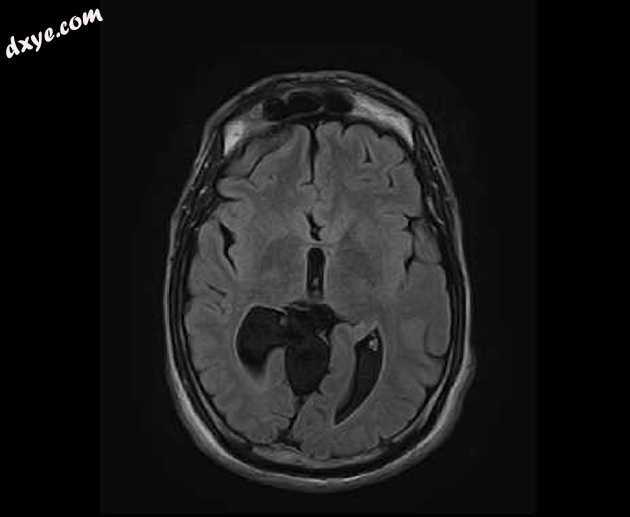

Axial FLAIR

MRI序列显示:

胼胝体弥漫性变薄

侧脑室的平行体

主要在右侧(头畸形)的三角和枕角扩张,在轴向序列上形成“泪珠”构型

小额角

半球间裂增宽

扩张的高位第三脑室

扩张的小脑上池

注意右眼假体。